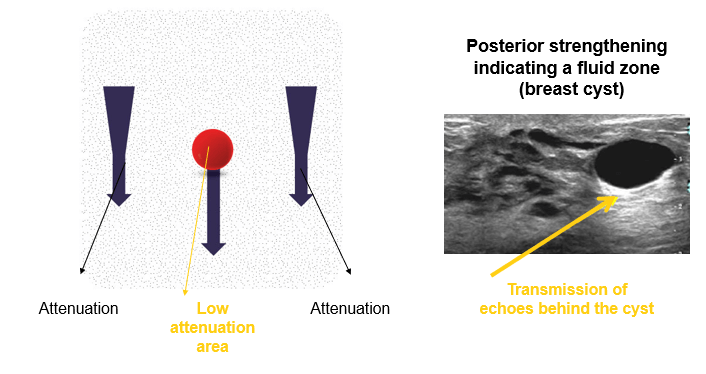

Posterior Strengthening

The second artifact is the posterior reinforcement artifact, which often occurs when the echo passes through a fluid zone (cyst).